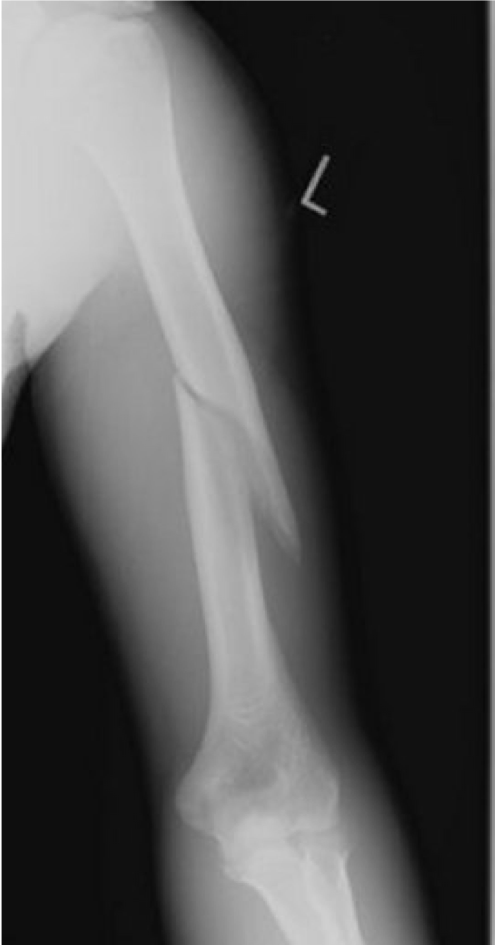

Clinical case: An 87 year old man fell at home. He had pain, deformity and bruising of his left arm. His X-ray is shown.

Which part of the humerus has been fractured?

What do you need to do in your examination of this patient?

During humeral shaft fractures that may affect the radial nerve, why is it better to test the motor function of the wrist than elbow?

As radial nerve comes down arm, the radial nerve has already given off some branches to triceps so will still get some extension at the elbow